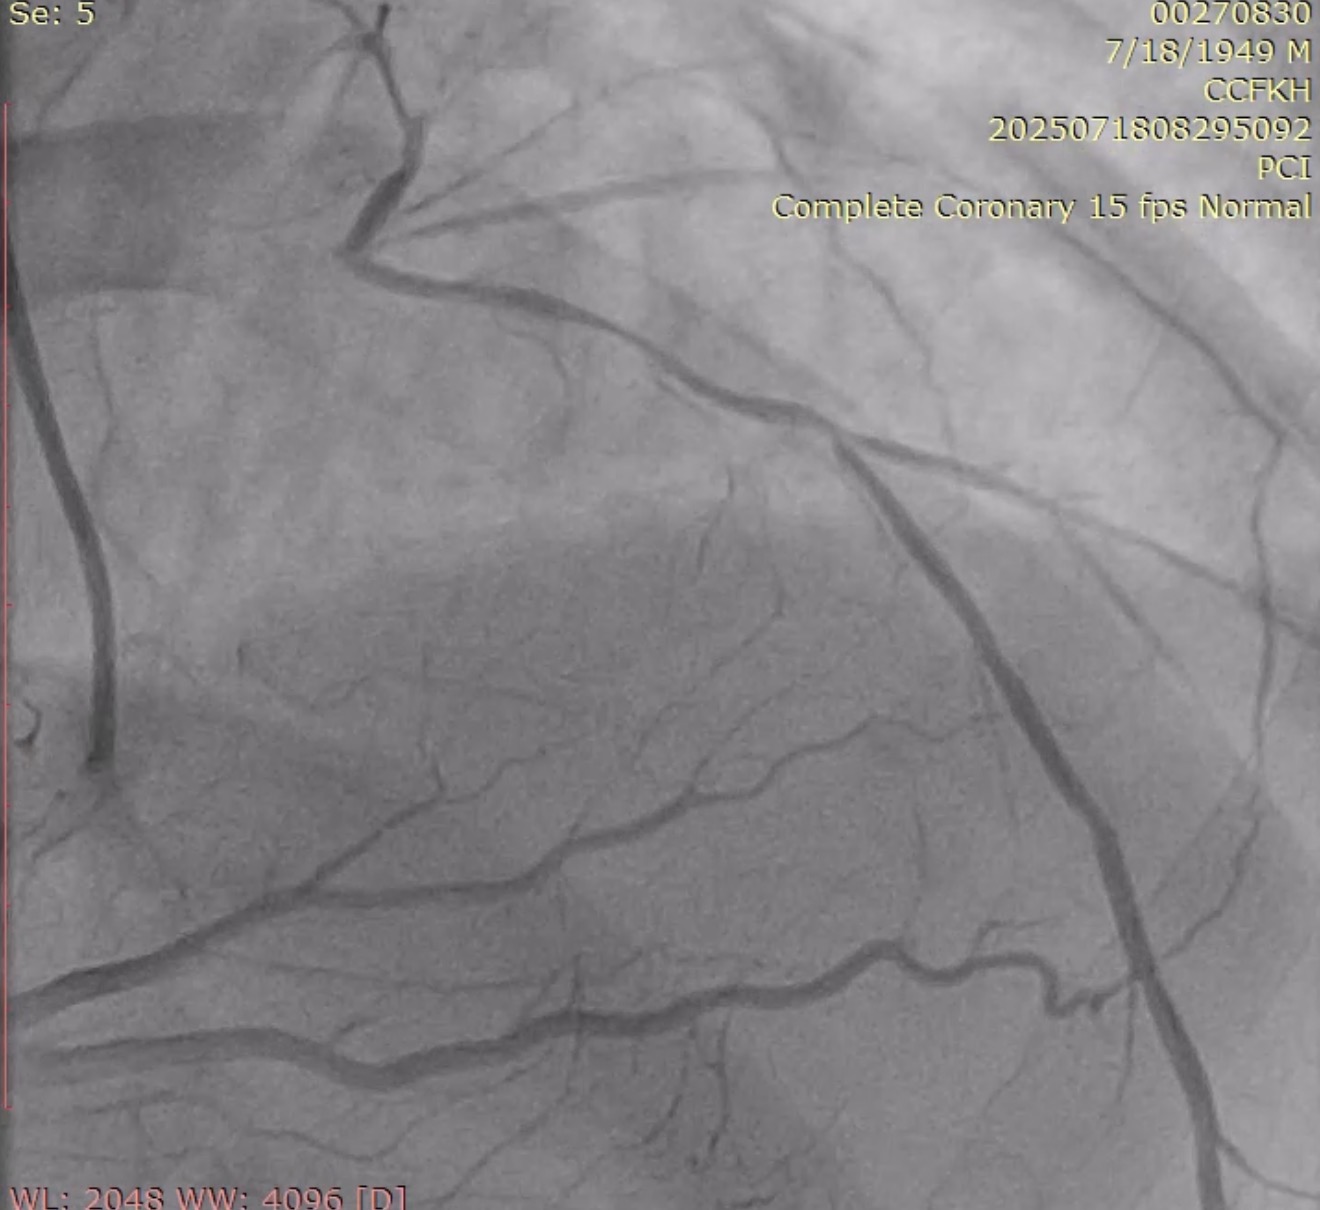

Urgent coronary angiography was performed by using right radial artery approach, which surprisingly showed left main coronary artery (LMCA) total occlusion with TIMI 0 flow. Right coronary artery has no significant stenosis with presence of excellent collaterals flow to the total left coronary system (Rentrop-3).

The left main was engaged by 6F EBU 3.5 via radial sheath. The LM occlusion was crossed by using workhorse guidewire (Cougar XT), suggesting an acute occlusion. Predilation with SC balloon (Sprinter Legend 1.5 x 12mm and Sprinter Legend 2.5 x 12mm) was performed at the occlusion site, resulting an antegrade flow from LM, but there was still no flow distally from mid-LAD.Plain old balloon angioplasty by Sprinter Legend 2.5 x 12mm performed at the mid-LAD, the flow from mid-LAD still was not achieved, giving the hypothesis of no reflow phenomenon. IC Nitroglycerine 100ug and IC Nicardipine 100ug were given several times, resulting a vasodilation and a better flow. It therefore revealed a significant competitive flow from powerful collaterals from the right coronary artery, ruling out the no reflow hypothesis (Refer to videos below for better illustration). Onyx Trucor DES 2.75 x 34mm, Onyx Trucor DES 3.0 x 22mm, and Onyx Trucor DES 3.5 x 22mm were implanted respectively from distal LAD to LM, and restored final TIMI 3 flow result